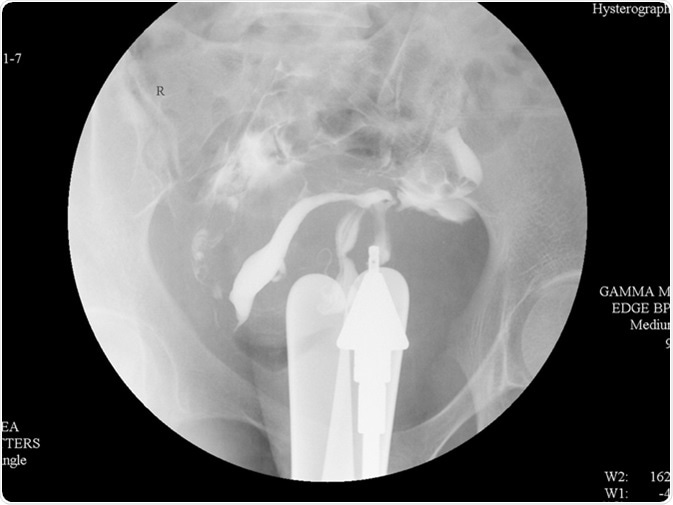

Hysterosalpingography (HSG) is a fluoroscopic X-ray study of a woman

Hysterosalpingography (HSG) is a fluoroscopic X-ray study of a woman's uterus and fallopian tubes. Image Credit: Whitetherock photo / Shutterstock